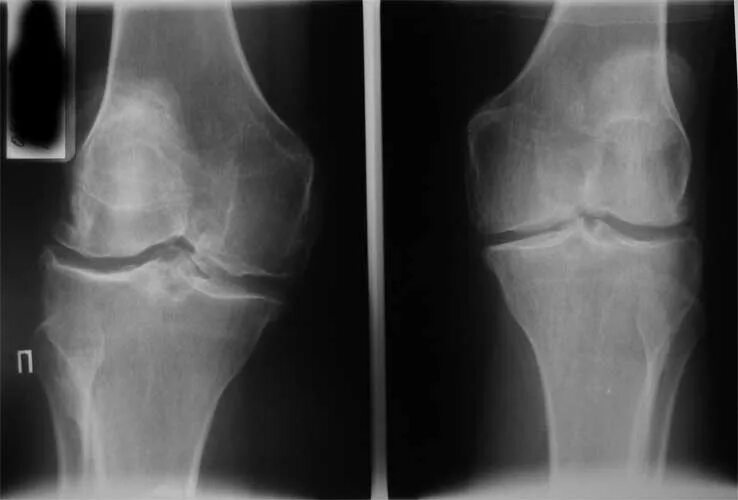

Рана коленного сустава мкб